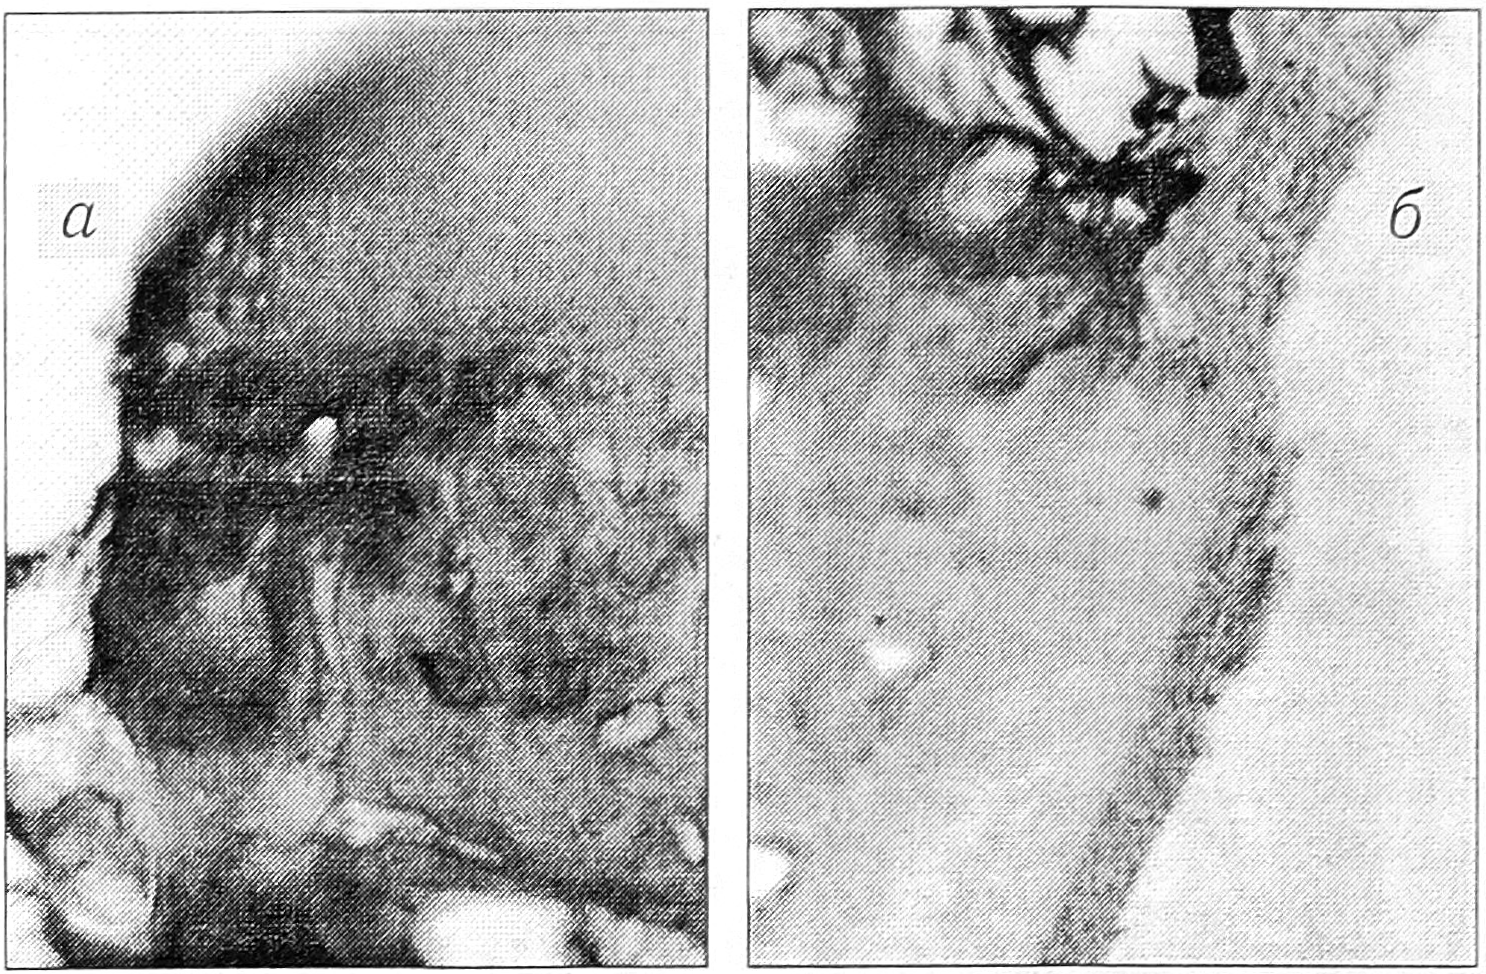

При гистологическом изучении препаратов, полученных через 7 дней после лазерного воздействия, выявлено следующее. В нагружаемых участках образовавшийся дефект проходит через всю толщу суставного хряща до субхондральной кости (рис. 1, а). По внутренним краям дефекта имеются обуглившиеся остатки тканей. На дне его определяются скопления фибрина. В пограничных с дефектом зонах поверхность суставного хряща неровная и разрыхленная, находящиеся здесь хондроциты не обнаруживают привычного для них горизонтального расположения. В средних слоях хрящевой пластинки значительная часть хондроцитов подвергается дегенеративным изменениям: определяются некроз ядер, отсутствие хондроцитов в лакунах. В нижней части хрящевой пластинки выявляются пролиферирующие клеточные элементы.

Рис. 1. Нагружаемый (а) и ненагружаемый (б) участки суставного хряща через 7 дней после воздействия лучом лазера.

Здесь и на рис. 2, 3: окраска гематоксилином и эозином, окуляр 7, объектив 8.

В пограничных с дефектом зонах суставного хряща его ненагружаемые участки подвергаются тем же изменениям, что и нагружаемые. При этом количество изогенных групп хрящевых клеток в них несколько больше, чем в нагружаемых участках. Сам дефект заполнен грануляционной тканью, выходящей в виде клинообразных разрастаний на суставную поверхность. Субхондральная костная ткань имеет сходную морфологическую картину (рис. 1, б).